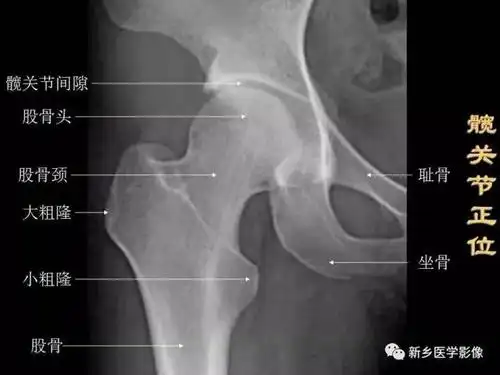

【收藏】髋关节x线解剖和摄影技巧

一文掌握正常髋关节x线解剖示意图